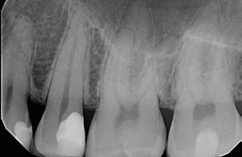

Bei dem 57-jährigen Patienten imponierte in der Routine-Bissflügelaufnahme eine Sekundärkaries an dem mit einem Gold-inlay versorgten Zahn 14 (Abb. 1). Der vitale und symptomfreie Zahn zeigte lediglich radiologisch (Abb. 2) einen Randdefekt distal sowie den Verdacht auf Karies unter dem Befestigungs- bzw. Unterfüllungszement. Nach Entfernung des Goldinlays ergab sich der Verdacht auf eine Pulpaeröffnung (Abb. 3). Klinisch war keine Blutung feststellbar, was allerdings durch die Lokalanästhesie kaschiert sein konnte. Aufgrund der Symptomlosigkeit des Zahnes und fehlender Anzeichen einer Pulpitis (fehlende Blutung) sowie einer Nekrose (erhaltene Vitalität) fiel die Entscheidung zugunsten einer Vitalerhaltung unter Beibehaltung eines engmaschigen Recalls mit Vitalitätsproben. Die Überkappung der Eröffnungsstellen erfolgte als Alternative zu Calciumhydroxid [8] mit einem Portlandzement enthaltenden Flowkomposit mit hohem pH-Wert [7,51] (TheraCal LC, Bisco, Abb. 4). Obwohl dieses Produkt hinsichtlich seiner Effektivität und Zelltoxizität nicht an ProRoot MTA (Dentsply Sirona) und Biodentine (Septodont) [42] herankommt [5,11], ist es hinsichtlich seiner Praktikabilität und der Möglichkeit des sofortigen, zügigen Weiterarbeitens konkurrenzlos. Ein vergleichbares Produkt gibt es z.B. bei Ultradent (Ultra- Blend Plus).